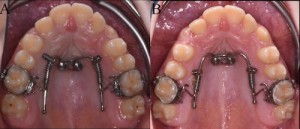

OBJECTIVES: The aim of the present case report is to describe an orthodontic treatment to gain space in the maxillary arch by using a bone-anchored molar distalization appliance (distal-jet)....

Authors:Michele Cassetta, Rosanna Guarnieri, Ersilia Barbato, Federica Altieri

OBJECTIVE: The aim of the present pilot study was to evaluate the efficacy of the miniscrew-supported distal jet appliance versus traditional distal jet appliance in terms of amount of upper first...